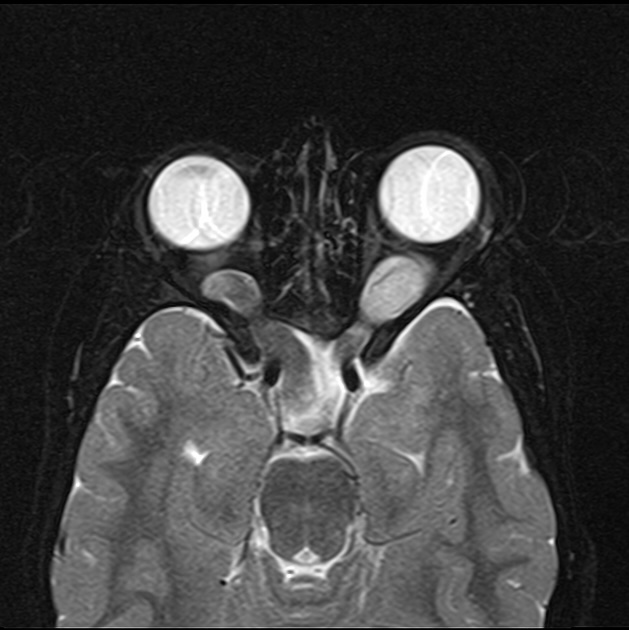

Магнитно-резонансная томография при подозрении на глиому хиазмы проводится в режимах Т1-взвешенных, Т2-взвешенных и диффузионно-взвешенных изображений с контрастным усилением. Обследование проводится в рамках нейровизуализации при нарушениях зрения, гипоталамических симптомах или признаках краниофарингиомы. Цель — детальное выявление анатомо-структурных изменений в области хиазмы зрительных нервов, определение характера опухоли, её распространения и степени компрессии окружающих структур.

На Т2-взвешенных изображениях — гиперинтенсивный сигнал от массы в области хиазмы и прилежащей части зрительных нервов, с признаками отёка или кистозной дегенерации.

Деформация и расширение хиазмы с вовлечением зрительных трактов или гипоталамических структур.

Нарушение симметрии зрительных нервов и зрительных трактов, их утолщение, искривление или смещение.